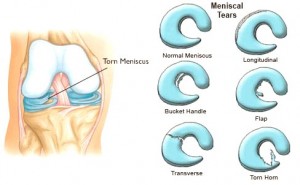

Types of Meniscal Tear

A meniscus tears in many different ways. The tears are determined in the way they look and the location of the injury. Some of these tears can be treated surgically and some are not.

• Frayed Edge

Damages caused by frayed edges are usually considered less serious. They are seen as ragged fronds at the sharp edges of a meniscus. Most surgeons correct these fray damages by trimming away the rough edges.

• Radial Tear

A radial tear is a sharp split in the inner rims toward the outer rims. This type of injury is usually treated through stitching but the inner injuries are less likely to heal because of poor blood supply but because this is the most important part of the meniscus, stitching is still the best option.

• Parrot Beak Tear

Parrot beak tear is an oblique shape type of neglected radial tear which may usually try to heal itself and may look like a parrot’s beak in time.

• Circumferential Tear

A circumferential tear is a tear that usually extends its length along the meniscus or the circumference.

• Bucket Handle Tear

When tears go through within the depths of the meniscus, these injuries have tendency to flip over the femur side which results to joint locking. These injuries can get worse and treatment is only through surgery.

• Horizontal Cleavage Tear

The horizontal split along the meniscus body is called horizontal cleavage tear. This is an unusual type of tear that may seem at first look just like a minor injury but in the deeper surface a bigger tear maybe present that can only be seen through an MRI scan.

• Flap Tear

Flap tear is a horizontal type of tear visible at the meniscus surface. It’s easier to be treated by just trimming the flap section away.